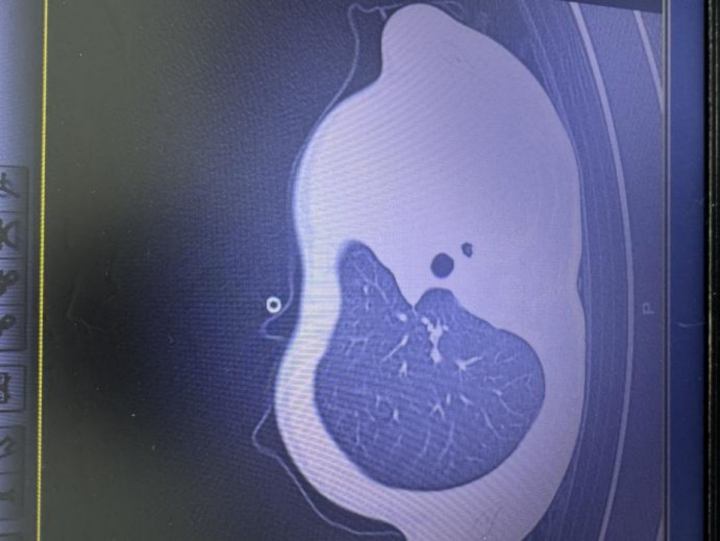

急诊检查结果让医护人员瞬间紧张:验血显示炎症指标大幅上升,胸片中发现左侧肺叶几乎“不工作了,影像学中变成大片白色,即通常所说的“白肺”,意味着肺功能严重受损,孩子已经缺氧,随时有窒息危险。

当天中午,小宇就被紧急送进PICU(儿科重症监护病房)。下午4点多,医生立即做了气管镜,镜下画面比预期的还要严重:气道里堵满了树枝状的黏稠痰栓,呼吸通道完全被塞住,气道内壁还有坏死组织。“呼吸内科医生在床边清理了一两个小时,才取出部分痰栓,但坏死组织还会继续引发堵塞,只能马上插管,靠呼吸机维持呼吸。”医生表示。

在ICU的10天里,小宇先后做了5次气管镜(12月2日、3日、5日、8日、11日),每次都需反复冲洗、清理新形成的痰栓和坏死组织,还通过穿刺抽出100多毫升胸腔积液,同时进行抗感染、抗炎等治疗。直到12月8日,小宇才撤下呼吸机,12月12日转入普通病房。目前孩子恢复良好,即将出院,但家人想起一天内病危的经历,仍感到后怕。